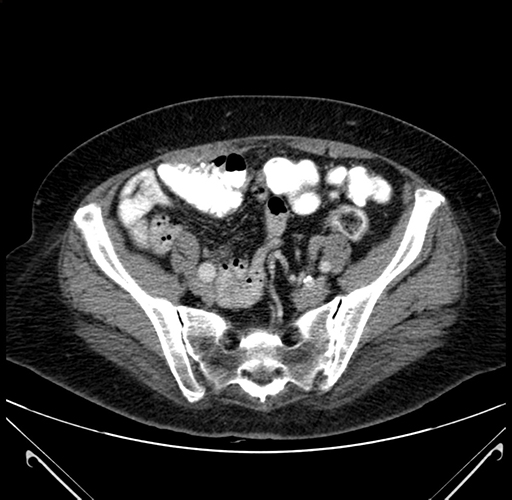

Axial Venous

Coronal Venous